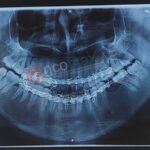

A 24 year old female patient reported to the department of Oral and Maxillofacial Surgery (OMFS) Supercare Hospital Shillong with Chief complain of severe pain in Bilateral TMJ and progressive development of open Bite. Her MRI of the condyle showed condylar hypoplasia with degeneration of the articular disc and reduced joint space.

The team of Oral and Maxillofacial Surgeons (who are a part of the OncomaxNE association) headed by Dr.Bobby L Majaw from Shillong and Dr. Ashutosh Vatsyayan from Guwahati carried out what is possibly the first ever CAD/CAM (Computer-aided – design/Computer-aided Manufacturing ) Alloplastic Bilateral Temporomandibular Joint replacement in a private set up in North East at Supercare Hospital, Shillong.

The custom fabricated implant was manufactured by TMJ Consultancy Services from Bhopal under the guidance of Dr.Darpan Bhargava. The operation lasted for 8 hours. Dr. PS Chakraborty, co-director of OncomaxNe and who is currently pursuing his MSc in Clinical Oncology at Birmingham, UK also expressed his happiness at the team’s success.